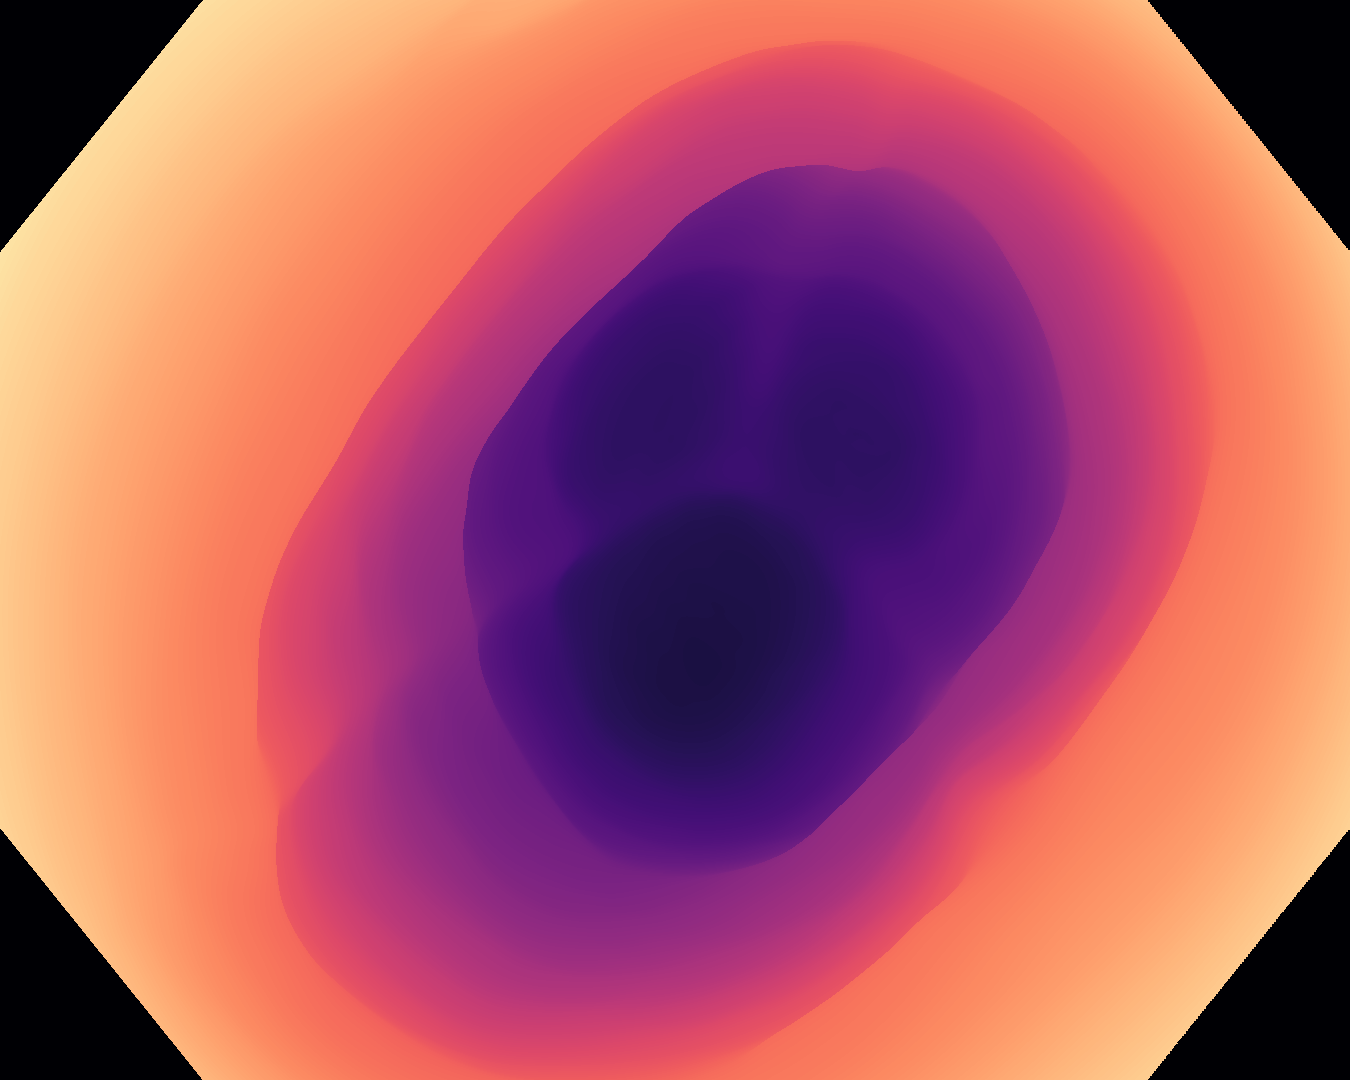

where NVsubscript𝑁𝑉N_{V} is the number of pixels covered by the lens in an image at its original size, y^i,jsubscript^𝑦𝑖𝑗\hat{y}_{i,j} is the value in the post-processed prediction for the jthsuperscript𝑗𝑡j^{th} pixel covered by the lens in the ithsuperscript𝑖𝑡i^{th} image at its original size, and yi,jsubscript𝑦𝑖𝑗y_{i,j} is the corresponding target value. For all metrics, a lower value indicates better performance. The results are presented in Table IX, and some examples are shown in Fig. 3 with corresponding error maps shown in Fig. 4 to help visualise the differences.

Input RN-HK-MC RN-HK-BT RN-IN-MC RN-IN-BT RN-IN-SL RN-NA-NA Refer to caption Refer to caption Refer to caption Refer to caption Refer to caption Refer to caption Refer to caption Refer to caption Refer to caption Refer to caption Refer to caption Refer to caption Refer to caption Refer to caption Input VT-HK-MC VT-HK-MA VT-IN-MC VT-IN-MA VT-IN-SL VT-NA-NA Refer to caption Refer to caption Refer to caption Refer to caption Refer to caption Refer to caption Refer to caption Refer to caption Refer to caption Refer to caption Refer to caption Refer to caption Refer to caption Refer to caption

Figure 4: Error maps for the post-processed predictions shown in Fig. 3, illustrating the absolute error with a larger value represented by a darker shade. For conciseness, we denote ResNet50s with RN, ViT-Bs with VT, Hyperkvasir-unlabelled with HK, ImageNet-1k with IN, MoCo v3 with MC, Barlow Twins with BT, MAE with MA, supervised pretraining with SL, and no pretraining with NA-NA.